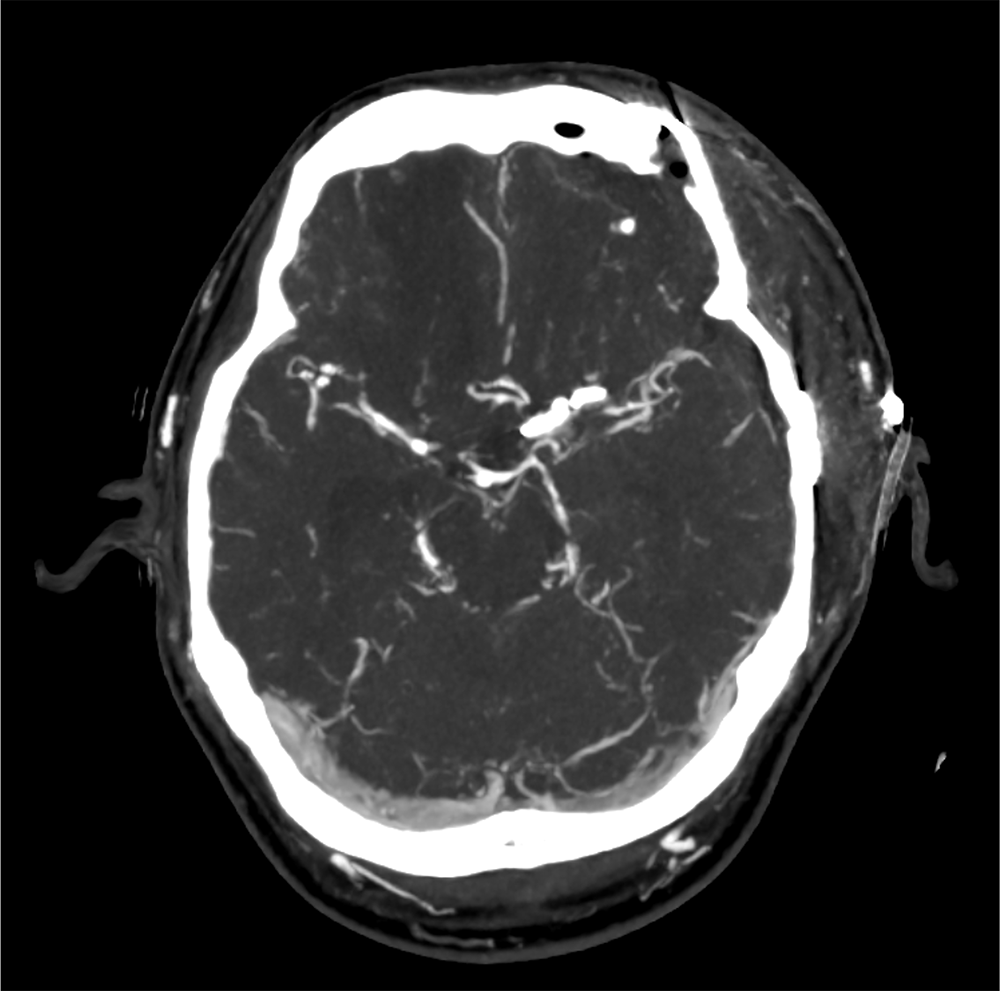

40歳代、男性、60kg、左内頚動脈瘤破裂、クモ膜下出血

左内頚動脈瘤破裂に対しクリッピング術後。術後評価のために頭部CTA、CTV、CT perfusion施行。

造影CTは、くも膜下出血の術前・術後評価の双方で用いられる。術前では破綻血管の同定や治療計画立案に、術後では再出血の有無や脳血管攣縮の評価に活用される。また発症前であっても、造影CTは動脈瘤の早期検出や血管構築の把握に寄与し、予防的観点からも重要な役割を果たす。

CT技術や撮像プロトコル設定について

術前では破綻血管の同定と治療計画に重点を置いたCTA撮影を、術後および経過観察では血管攣縮や虚血評価を目的としたCBP撮影を選択する。これらを組み合わせることで、診断から治療戦略決定、さらには予後予測まで一貫した画像診断が可能となる。